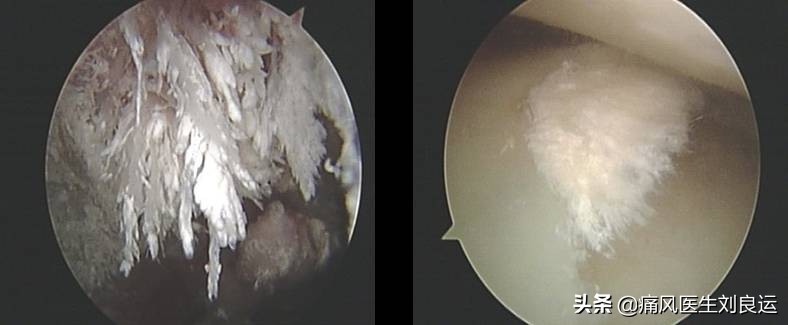

针刀镜下尿酸盐结晶

痛风发作主要是由于体内的尿酸升高导致析出的尿酸盐结晶在关节处沉积造成的炎症反应。临床上,也把有没有尿酸盐结晶作为判断痛风的关键。就是说,引起疼痛的不是尿酸高这么简单,而是尿酸盐结晶沉积后对关节造成的侵蚀。尿酸盐结晶在关节及其周围组织中的沉积是痛风发作的始动因素,不但引发天然免疫反应,而且可对局部组织造成直接损伤,加重局部炎症。

- 1.针刀镜快速降尿酸:治疗痛风需要以各种途径加速体内的尿酸结晶排出。单纯的药物治疗能起到溶解部分尿酸盐结晶并协助排出,但沉积在关节中的尿酸结晶单靠药物难以完全清除。就痛风性关节炎而言,减少尿酸生成、促进其排泄是治疗的根本,针刀镜通过关节内滑膜、软骨表面钝剥以及关节腔内的充分灌洗,可以清除关节滑液及滑膜、软骨表面的致炎因子、纤维素、纤维连接蛋白、沉积的免疫复合物等,在消除针刀镜所治疗的关节局部炎症的同时,减少关节局部免疫原性复合物对机体免疫应答反应,调控自身免疫紊乱,遏制风湿病全身病情的进展。同时通过解除关节内外的组织粘连、削剥增生的滑膜,清除血管翳或尿酸盐结晶,可以迅速、明显的改善关节活动度,尤其是膝关节,双侧膝关节腔内的关节滑膜,可以占到全身关节滑膜的50%以上,双膝关节腔的灌洗、滑膜的削剥以及药物的灌注,对于缓解全身的风湿病病情大有益处。对局部关节进行针刀镜诊治,一则进一步明确病情及诊断,二则通过关节腔冲洗、部分痛风石刮除及关节松解能够迅速缓解关节红肿热痛的炎症反应、改善关节功能,序贯以经筋刀等治疗,能够疏通经络,进一步改善症状。

针刀镜下痛风治疗